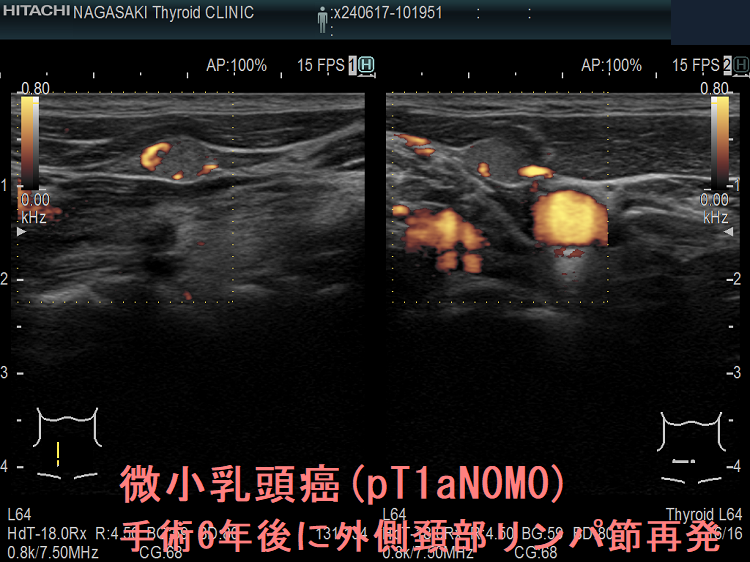

ケース①

ケース②